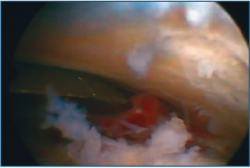

Primero, realizamos limpieza de tejidos blandos y localizamos el flexor hallucis longus (FHL), que será el límite medial de seguridad. Recordamos que, en las fracturas de grado II de Sanders (Figuras 1 y 2), permanece íntegro un gran fragmento anteromedial, mientras que el fragmento posterolateral se desplaza. Tras la limpieza, identificamos la fractura (Figura 3) y movilizamos el fragmento lateral. Luego cambiamos los portales e introducimos el artroscopio por el portal medial, que nos permite acceder hasta el seno del tarso y visualizar el ligamento interóseo talocalcáneo. A través de un pequeño abordaje en la cara lateral del calcáneo reducimos la articulación subastragalina posterior (Figura 4A).

Figura 3. Visión artroscópica del apoyo del instrumental en el fragmento anteromedial durante la reducción de la fractura.